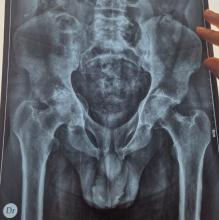

D’après : Bouvard B, Legrand E. Ostéoporose : encore trop ignorée ! Rev Prat Med Gen 2025;39(1100);381-91.